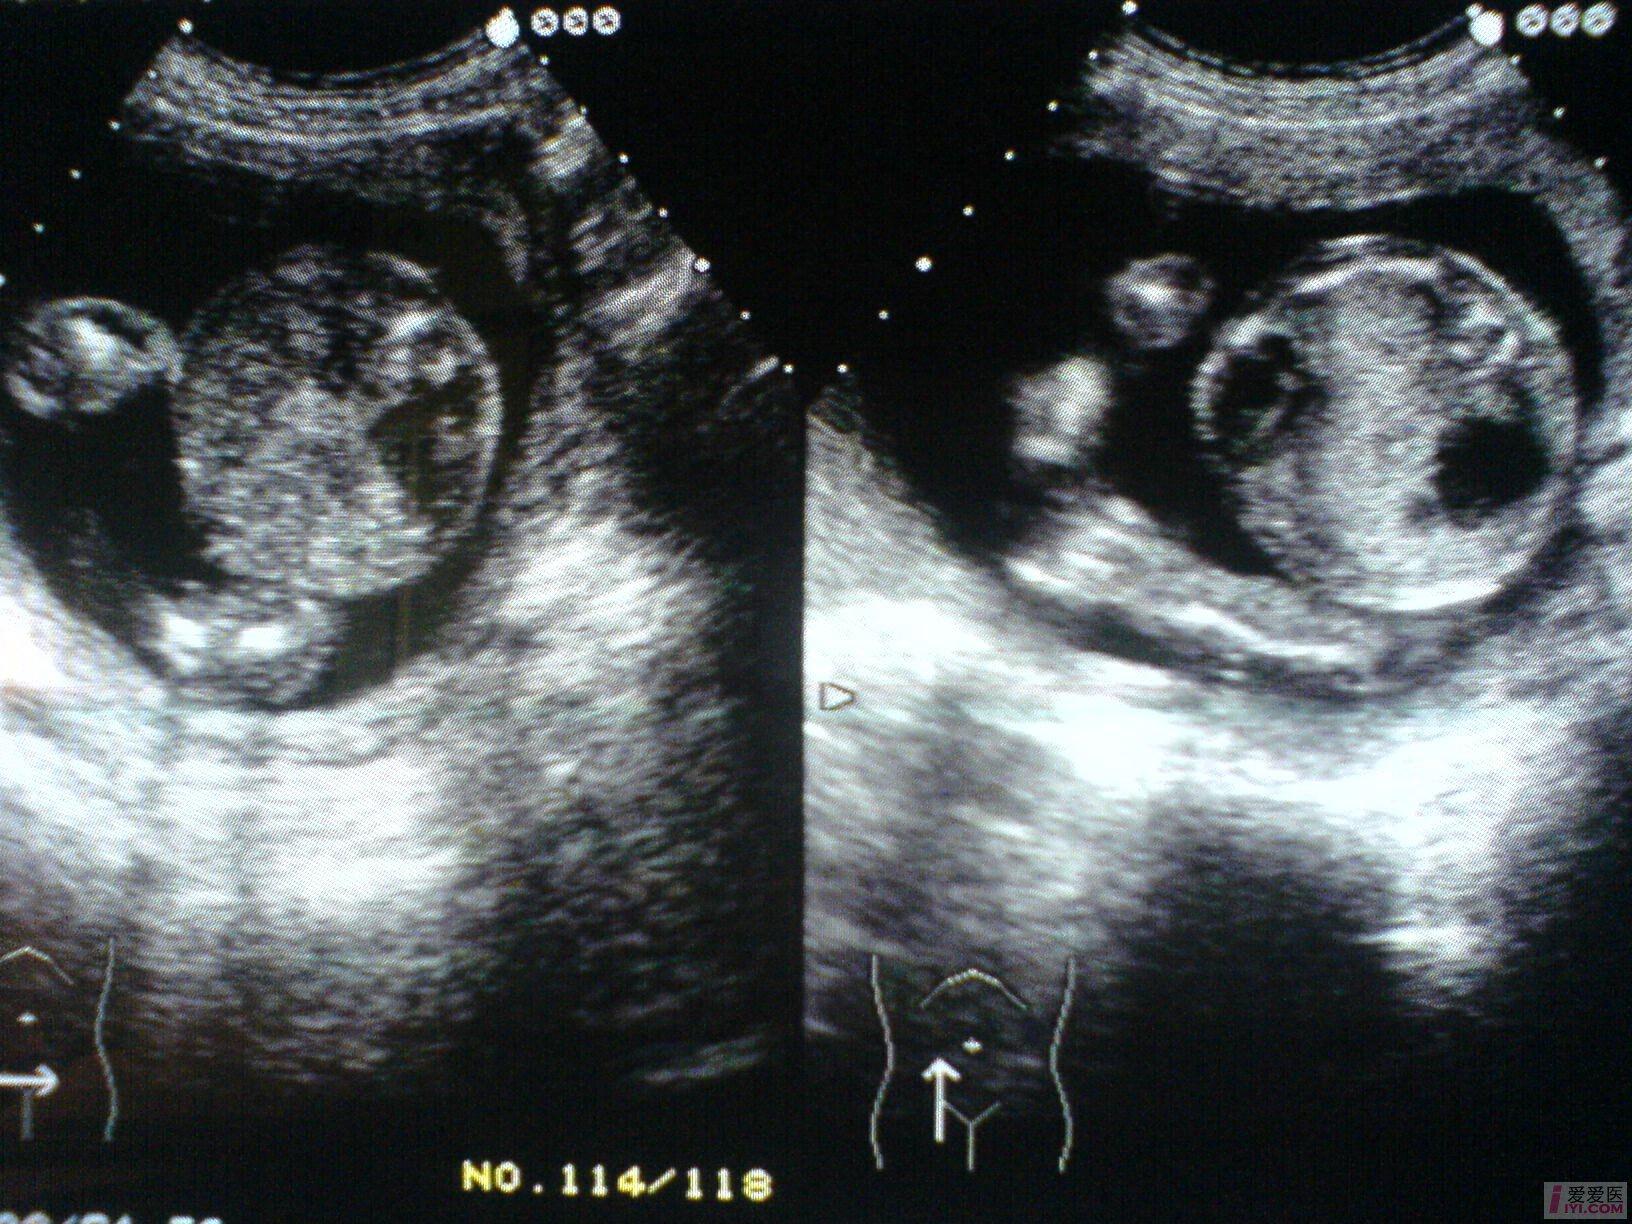

孕妇,女,33岁,G2P1,孕21周,常规产检。

B超所见:宫内单胎妊娠,胎头双顶径51mm,股骨长35mm,胎儿脊柱完整,肺实质回声增强,右侧肺叶内见31X18X17mm不规则无回声区,边界清晰,内透声好,CDFI:无回声区内未见血流信号。胎儿心胸比例失常,心脏明显受压,胎儿肝脏增大,位置下移,占据整个腹腔,回声增粗,欠均匀,未见胃泡回声,肝脏周围见宽4mm无回声暗区。胎动活跃,胎心搏动好,胎心律150bpm,胎盘附于前壁,厚21mm,回声均匀,最大羊水暗区深度74mm,透声好。

B超提示:1.宫内中孕,单胎存活,胎儿发育符合21周。

2.胎儿肺实质回声增强,右侧肺叶囊性占位,肝大,少量腹水。

请教:该例病例可否考虑胎儿肺囊腺瘤样变? [readperm]1[readperm]